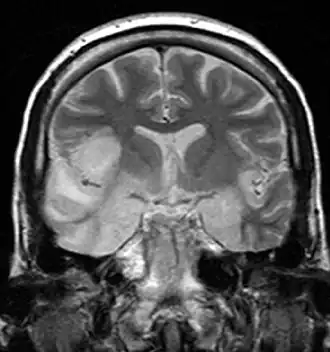

Герпетический энцефалит Герпетическая инфекция мозга, которая, как предполагается, вызывается ретроградной передачей вируса по аксону тройничного нерва в мозг. HSV является наиболее распространённой причиной вирусного энцефалита. Вирус накапливается преимущественно в височных долях[10].